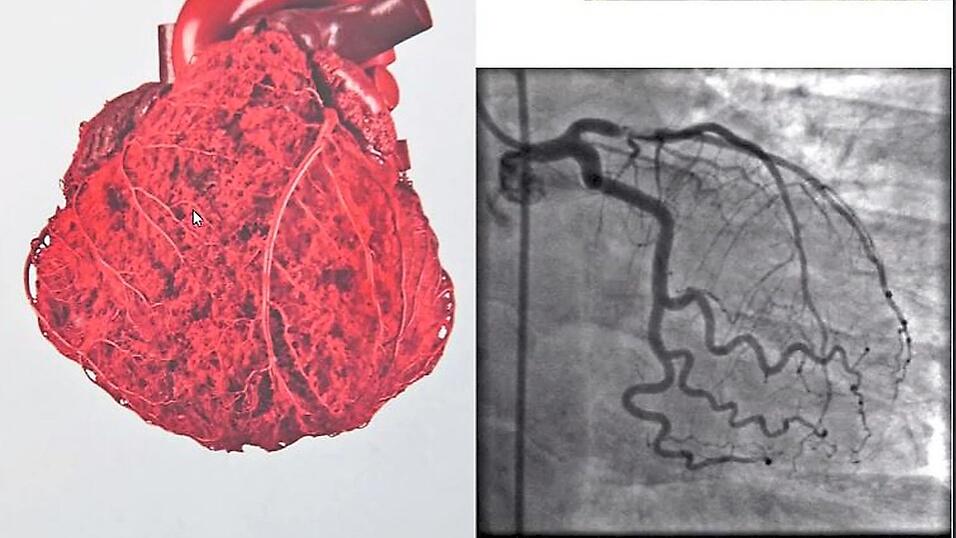

Der Herzmuskel wird von den Herzkranzgefäßen mit Blut versorgt. Mit MRT-Aufnahmen können Ärzte erkennen, ob das Organ gut durchblutet und frei von Entzündungen ist. Covid-Patienten erleiden während ihrer Infektion bis zu 20 mal häufiger eine Herzmuskelentzündung, als Impflinge nach der 2. Spritze.